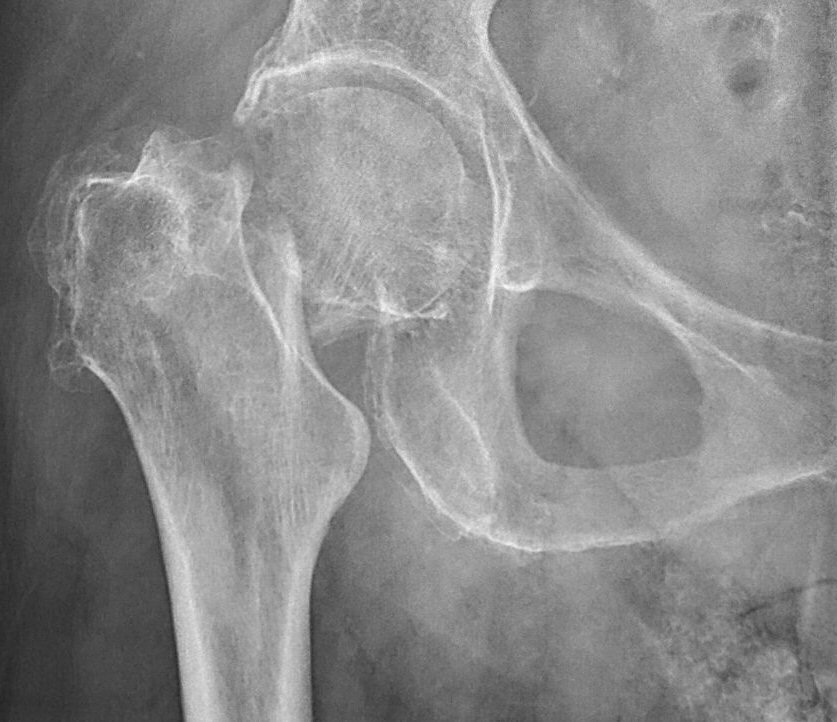

- Cervikal, fraktur av kollum femoris. Klassificeras enligt Garden som bedöms på frontalbild. Det finns något olika tolkningar av denna klassifikation. Ofta används istället "Garden 1-2" för odislocerad eller måttligt dislocerad fraktur och "Garden 3-4" för mer dislocerad.

- Garden 4: genomgående fraktur, parallellförskjuten, kaput ligger rätt i acetabulum [1]